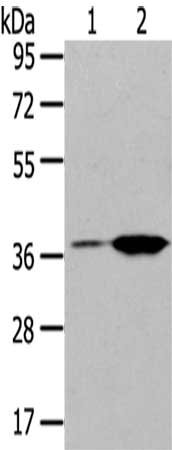

Gel: 8%SDS-PAGE,Lysate: 40 μg,Lane 1-2: Raji cells, Jurkat cells,Primary antibody: CSB-PA550037(TBXA2R Antibody) at dilution 1/200 dilution,Secondary antibody: Goat anti rabbit IgG at 1/8000 dilution,Exposure time: 40 seconds